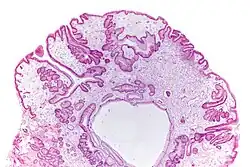

| Micrograph of a gastric juvenile polyp, as may be seen in juvenile polyposis syndrome. H&E stain | |

Juvenile polyposis syndrome is an autosomal dominant genetic condition characterized by the appearance of multiple juvenile polyps in the gastrointestinal tract. Polyps are abnormal growths arising from a mucous membrane. These usually begin appearing before age 20, but the term juvenile refers to the type of polyp (i.e. benign hamartoma, as opposed to adenoma for example), not to the age of the affected person.[1] While the majority of the polyps found in juvenile polyposis syndrome are non-neoplastic, hamartomatous, self-limiting and benign, there is an increased risk of adenocarcinoma.